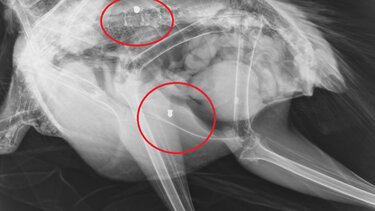

Το εντυπωσιακό πτηνό φέρεται να δέχθηκε πυροβολισμούς, γεγονός που επιβεβαίωσαν και σχετικές ακτινογραφίες που "έδειξαν" μάλιστα δυο βολίδες αεροβόλου κι ένα σκάγι.

Το παγώνι φέρεται να δέχθηκε πυροβολισμούς, γεγονός που επιβεβαίωσαν και σχετικές ακτινογραφίες που "έδειξαν" μάλιστα δυο βολίδες αεροβόλου κι ένα σκάγι.

"Το ζώο αυτό έχει πυροβοληθεί τρείς φορές, την ίδια ώρα ή διαφορετικές δεν μπορούμε να ξέρουμε, ούτε αν ο δράστης είναι ένας ή δύο ή τρεις, μέσα ή δίπλα σ έναν από τους πιο πολυσύχναστους αρχαιολογικούς χώρους της Κρήτης και της Ελλάδας γενικότερα" αναφέρει χαρακτηριστικά σε ανάρτηση του ο Σύλλογος ΑΝΙΜΑ.